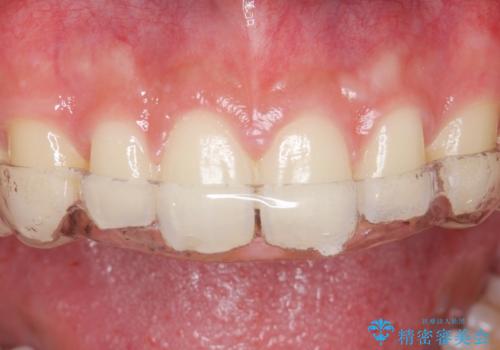

ノンクラスプデンチャー

治療症例の内容

- 以前から治療されている患者様です。

左上の小臼歯、大臼歯が欠損しているため。インプラントのご案内をさせてもらったところ外科的な処置は行いたくないとの事でしたので

部分入れ歯のご案内をしました。なるべく銀は見えたくないとの希望により保険の入れ歯ではなく自費の入れ歯(ノンクラスプデンチャー)を作製しました。

ノンクラスプデンチャーは保険の入れ歯に比べて異物感が少なく、またメタルの部分も少ないので目立ちません。